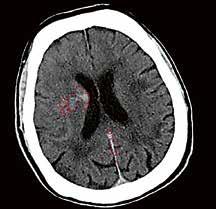

Gehirnblutung oder Gefäßverschluss

Handelt es sich um eine intrakranielle Blutung oder ist ein großes Gefäß verschlossen?

Ein Schlaganfall kann auf unterschiedliche Ursachen zurückzuführen sein. Deshalb ist es besonders wichtig, in kürzester Zeit über eine aussagekräftige Diagnostik zu verfügen.

Mit der Deep-Learning-basierten Auto-Stroke-Solution bringt Canon eine Lösung auf den Markt, die nicht nur selbstständig Bilder erstellt, sondern auch noch den Befundbericht dazu liefert.

jedes einzelne Pixel. Die Software stellt sogar selbstständig fest, ob die Untersuchung mit oder ohne Kontrastmittel durchgeführt wurde.“ Handelt es sich um eine Untersuchung ohne Kontrastmittel, sucht Auto-Stroke nach einer Gehirnblutung und erkennt selbstständig die unterschiedlichen Arten: subdural, epidural oder subarachnoidal. Wurde bei der Untersuchung Kontrastmittel verwendet, sucht die Maschine nach einem Gefäßverschluss. Und auch Perfusionsstudien werden automatisiert ausgewertet. Sowohl die ausgewerteten Bilder als auch die maschinell erstellten Reports werden direkt ins PACS geschickt. Man kann das System auch so einstellen, dass es den Report per E-Mail entweder an die behandelnden Ärzt*innen oder zusätzlich an die Radiolog*innen versendet. Im PDF-

Befundbericht sind in den Bildern die verdächtigen Areale markiert beziehungsweise farblich hervorgehoben, so dass leicht zu erkennen ist, wo eine Veränderung stattgefunden hat.